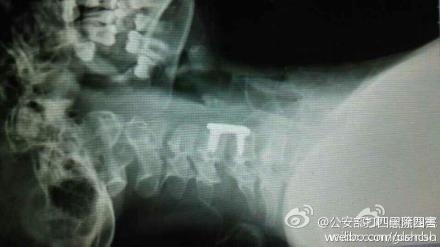

受伤的这名女孩家住邯郸。昨日早上,在家人的无比焦急中,女孩小青被紧急送至省三院就诊。经过专家们的仔细诊断和全面会诊,小青的颈椎已经完全断裂,这意味着小青很可能会高位截瘫。

专家们通过询问得知,导致这一悲剧的原因是小青在乘坐电动车时,由于其所佩戴的围巾较长而被绞进电动自行车车轮里。“12月2日下午,小青戴着长围巾乘坐电动车时,长围巾被车轮绞住。在惯性作用下,小青的脖子被紧紧勒住,电动车停下后,小青感觉自己不能动了,而且呼吸也变得非常困难。”专家们说,小青随即被送至当地医院进行紧急抢救,可由于其病情较重当地医院遂建议其到石家庄就医。

当小青被送到石家庄时,距悲剧已发生了15个小时,一轮紧张有序的检查后,小青被送进医院手术室。不幸中的万幸,手术进行得很成功。但由于脊柱断裂,小青的全身已瘫痪。同时,意外还影响到了肌肉,小青已经不能自主呼吸,目前只能通过呼吸机辅助呼吸。